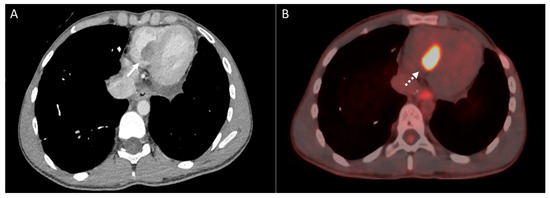

2.2. Vascular Metastasis

5. Cardiac and Major Thoracic Vessels